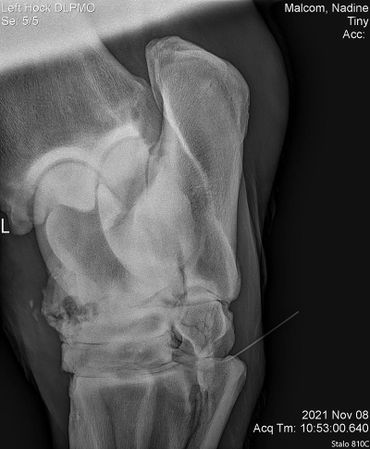

Tiny showed some stiffness in his left hind so we did x-rays on his hock on 11/09/2021. He's got some serious arthritis going on in there so he got injected to make him feel more comfortable especially with winter coming.

Now, three weeks down the road we enjoy seeing him move so much better and actually anticipating in the plays the geldings have with each other.

His vet bill was $585. Any contribution towards his bill would be greatly appreciated!